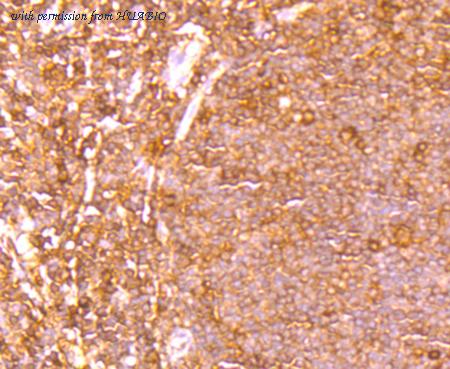

image 2 :

Immunohistochemical analysis of paraffin-embedded human tonsil tissue using anti-ETS1 antibody. The section was pre-treated using heat mediated antigen retrieval with Tris-EDTA buffer (pH 8.0-8.4) for 20 minutes.The tissues were blocked in 5% BSA for 30 minutes at room temperature, washed with ddH2O and PBS, and then probed with the primary antibody (ET1705-23, 1/50) for 30 minutes at room temperature. The detection was performed using an HRP conjugated compact polymer system. DAB was used as the chromogen. Tissues were counterstained with hematoxylin and mounted with DPX.